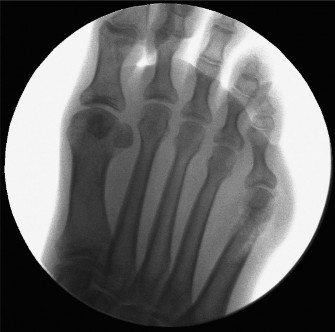

- Radiographic Evaluation:

- Weight-Bearing X-rays: Essential for proper classification and surgical planning. Obtain standard views:

- Anteroposterior (AP): Measure the 4-5 intermetatarsal angle (IMA, normal < 8-9 degrees), assess the contour of the fifth metatarsal head, and evaluate the lateral bowing of the fifth metatarsal shaft.

- Lateral: Assess the fifth metatarsal head articulation and any plantarflexion of the fifth metatarsal.

- Oblique: Provides the best view of the lateral condyle of the fifth metatarsal head and shaft for Type I bunionettes. This view is crucial for identifying the extent of hypertrophy.